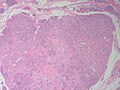

Fibroadenoma. H&E stain. | |

Features:[3]

- Abundant (intralobular) stroma - most key feature.

- Stroma is usually:

- White/pale, i.e. myxoid, on H&E (normal stroma is pink).

- May be hyalinized (dark pink) if infarcted.

- Paucicellular - typical.

- Compression of glandular elements - very commonly seen.

- Glandular elements have at least two cell layers - epithelial and myoepithelial.